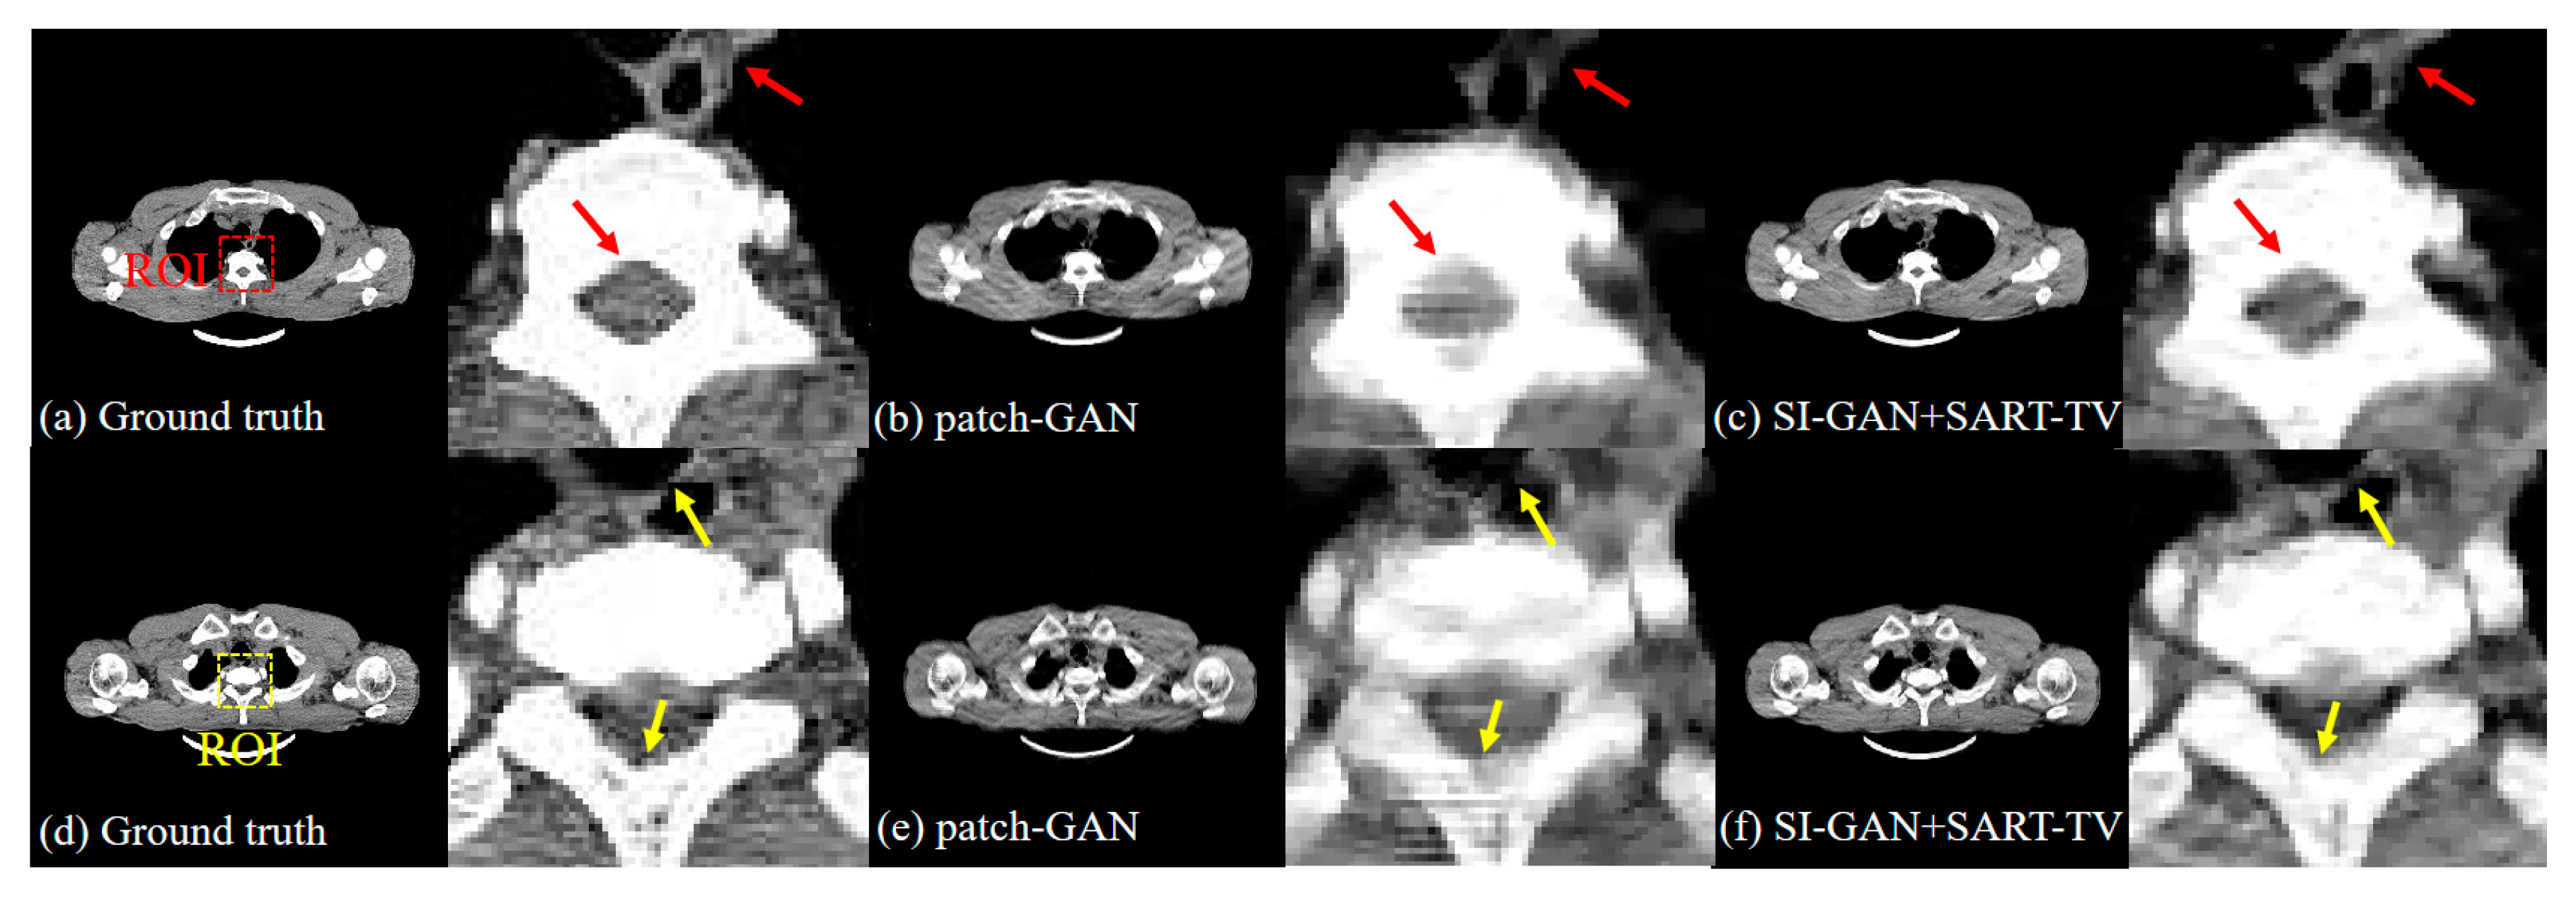

| avg. PSNR | avg. RMSE | avg. NMAD | avg. SSIM | |

|---|---|---|---|---|

| FBP | 17.234 | 0.0553 | 1.5684 | 0.2631 |

| SART-TV | 18.792 | 0.0317 | 0.6512 | 0.7479 |

| patch-GAN | 28.369 | 0.0131 | 0.1828 | 0.9433 |

| SI-GAN () + FBP | 27.230 | 0.0164 | 0.3493 | 0.8513 |

| SI-GAN () + SART-TV | 28.122 | 0.0139 | 0.1933 | 0.9466 |

| SI-GAN + FBP | 29.209 | 0.0114 | 0.2689 | 0.8657 |

| SI-GAN + SART-TV | 31.052 | 0.0093 | 0.1264 | 0.9648 |